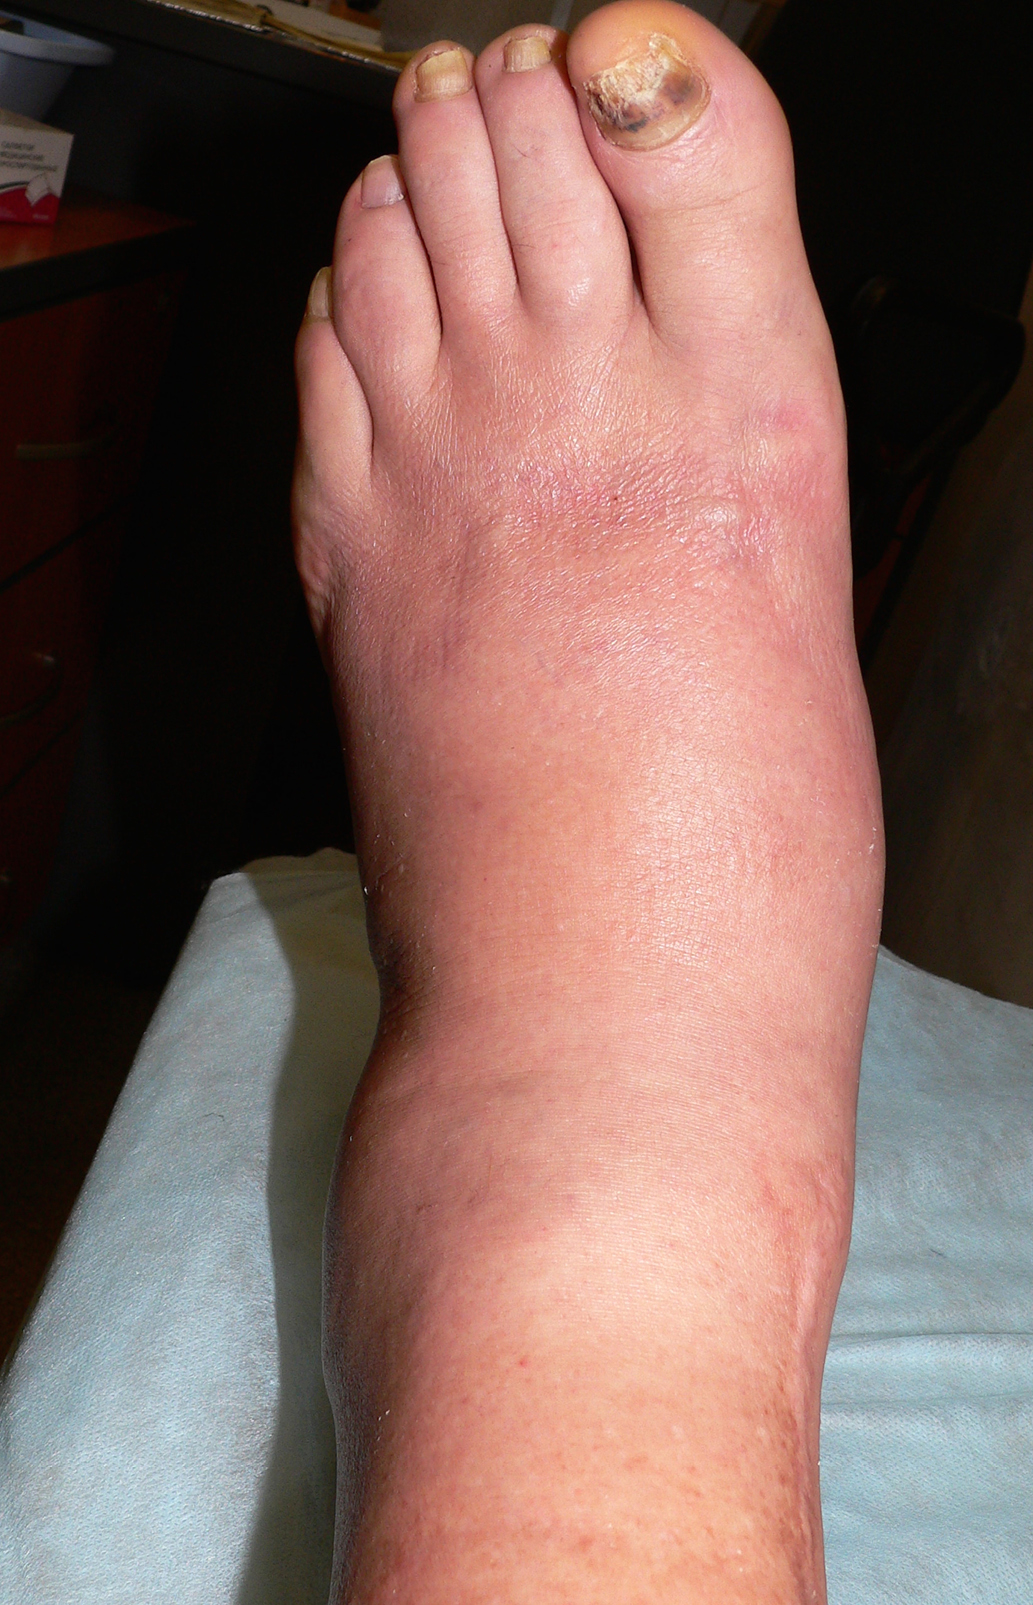

Рост 171 см, масса тела 92 кг. Определяется отек левой стопы и голеностопного сустава, пульсация артерий стоп справа ослаблена, слева отсутствует (рис. 1). Чувствительность к 10-граммовому монофиламенту, вибрационная, болевая и температурная чувствительность отсутствуют. Ахилловы рефлексы не вызываются. Балл по шкале модифицированного Нейропатического Дисфункционального Счета (НДСм)=10. Температурный градиент в пользу левой стопы=4,1°С. Отчетливой деформации продольных сводов стоп нет при уплощении поперечных сводов.

Рис. 1. Стопа пациента 1 при первом осмотре.